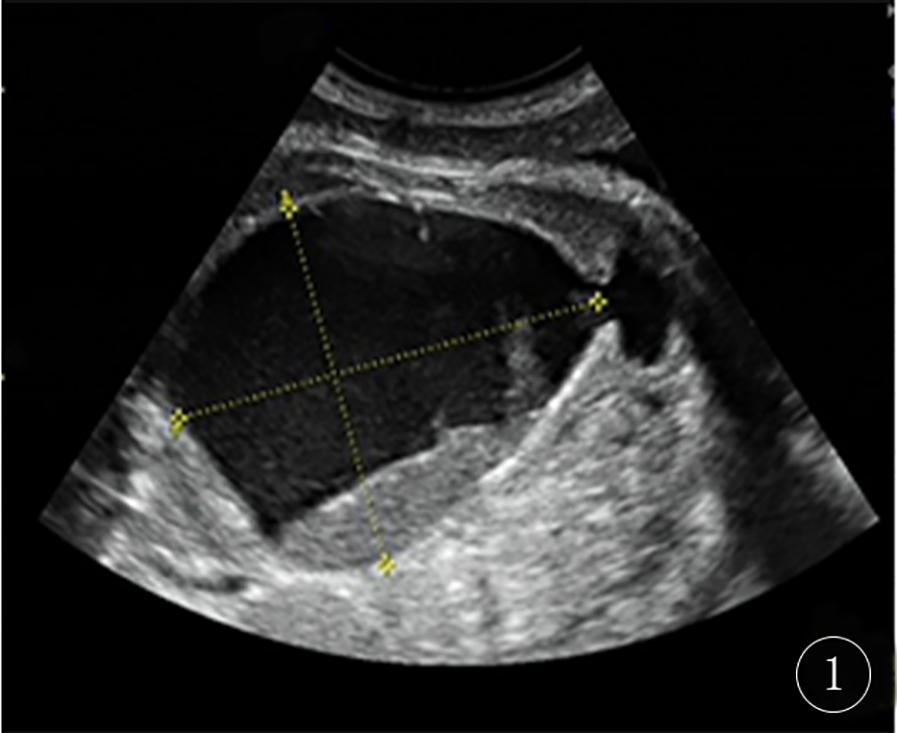

A 29-year-old gravida 0, para 0, female patient at 37 weeks + 3 days (October 23, 2024) gestation presented to the Jiaxing Maternal and Child Health Care Hospital for routine prenatal ultrasound examination. The prenatal ultrasound revealed that the fetal bladder measured 4 mm × 64 mm × 83 mm (Figure 1), with internal septations and echogenic debris. The posterior wall of the bladder showed a 40 mm × 11 mm heterogeneous, slightly hyperechoic area. Bilateral umbilical arteries were visualized, and a 47 mm × 37 mm × 44 mm anechoic area was noted anterior to the left side of the bladder. No dilatation of the renal pelves or ureters was observed.

Figure 1

Fetal ultrasound at 37 weeks + 3 days the image shows a large cystic mass, approximately 64 mm × 83 mm in size, within the fetal pelvis. The cyst contents exhibit heterogeneous echogenicity.